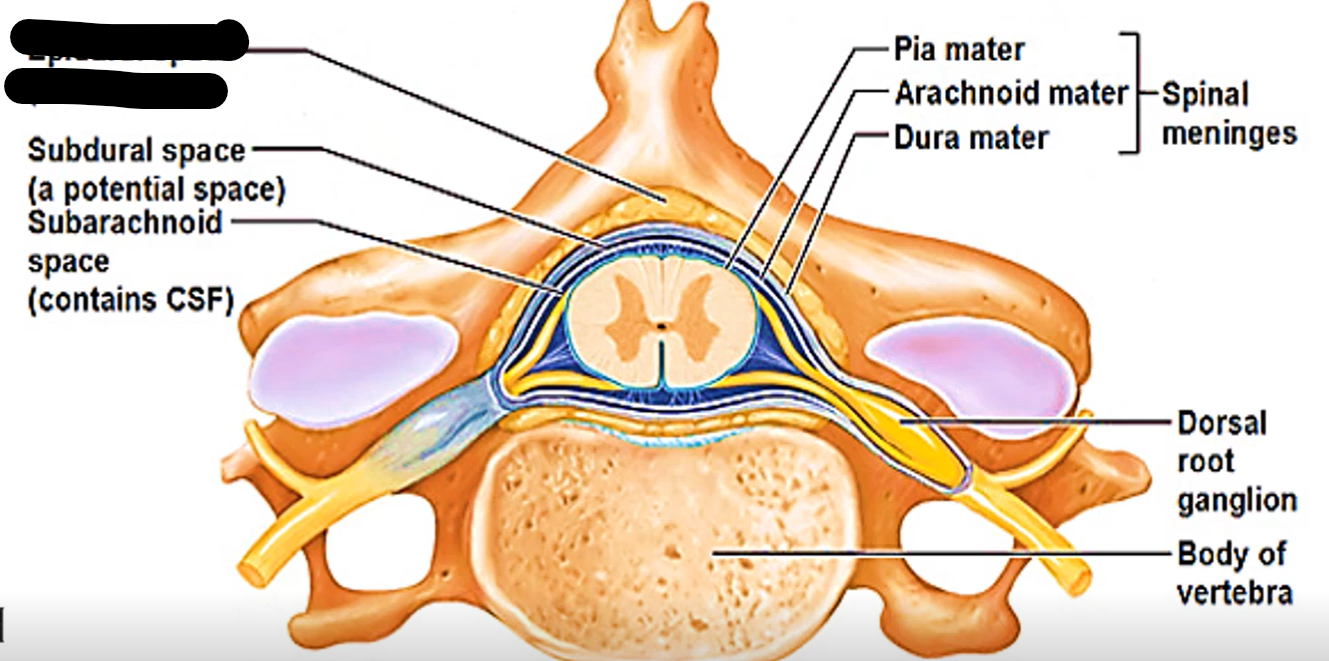

How many layers of meninges

3

Layer of meninges from superficial to deep

Dura mater

Arachnoid mater

Pia mater

What are the two layers of dura mater?

Periosteal dura mater

Meningeal dura mater

Where is epidural and subdural space?

In spinal cord (contains fat) or brain (potential space)

What does epidural space separate in spinal cord?

Between vertebrae and dura mater

Epidural space (contains fat)

Subdural space (contains CSF)

What does subdural space separate?

Dura mater and arachnoid mater

What does subarachnoid space separate?

Arachnoid mater and pia mater